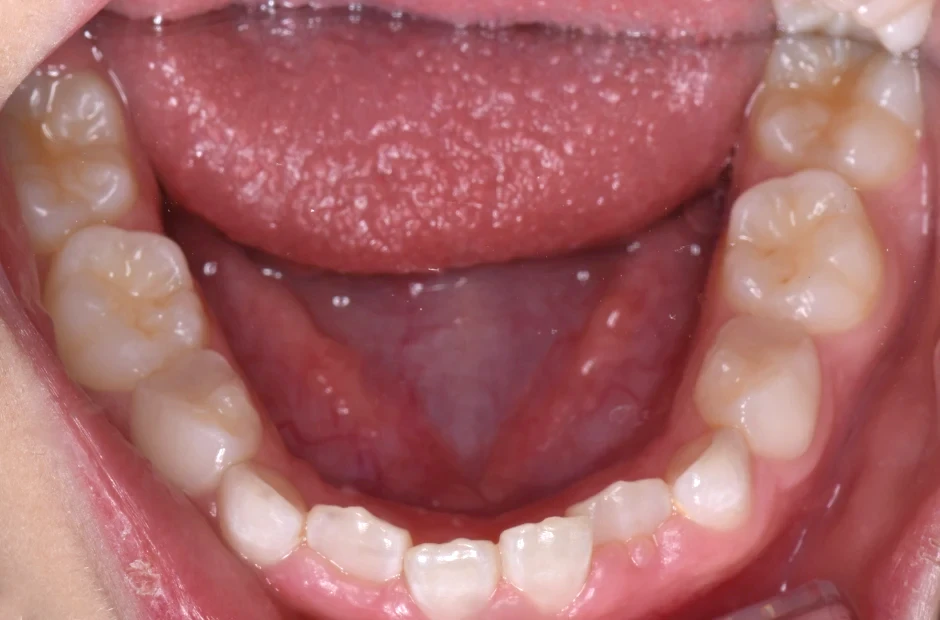

前歯部反対咬合とすきっ歯

| 診断名・主訴 | 前歯部反対咬合とすきっ歯 |

|---|---|

| 年齢・性別 | 7歳・女性 |

| 治療期間・回数 | 1年半、月一回 |

| 治療に用いた主な装置 | 床拡大装置+ブラケット(前歯部) |

| 抜歯部位 | なし |

| 治療費 | 30万円(税抜) |

| リスク・副作用 | 装置による違和感・疼痛・歯肉退縮・歯根吸収・虫歯のリスクなど |

治療前

治療後